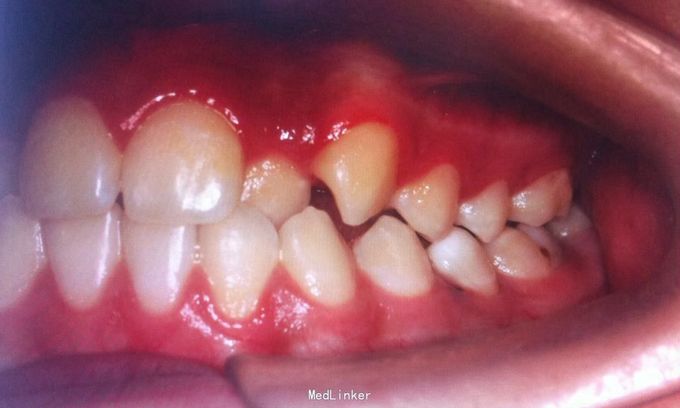

恒牙期 左右磨牙近中关系 12,22舌侧错位 32、33融合牙 右侧磨牙反合 上下牙列轻度拥挤 关节有弹响

安氏三类、后牙反合 不拔牙矫治,直丝弓矫治器,排齐整平上下牙列,解除后牙反合,矫治后覆合覆盖正常,磨牙中性关系,维持现有面型